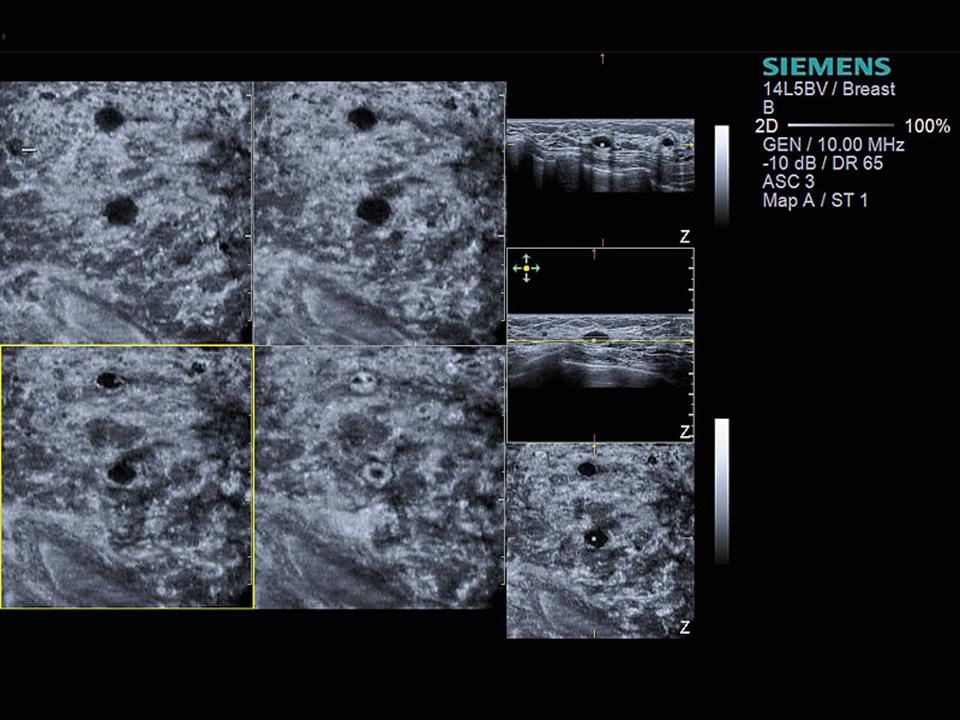

Ultrasound

Clear analysis of dense breast tissue